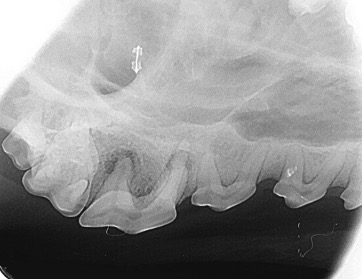

L’examen oral n’est pas complet sans une évaluation réalisée sous anesthésie et accompagnée de radiographies dentaires, car environ 60% de la dent se situe sous la gencive, invisible à nos yeux. Un diagnostic dentaire précis nécessite donc l’aide de l’imagerie.